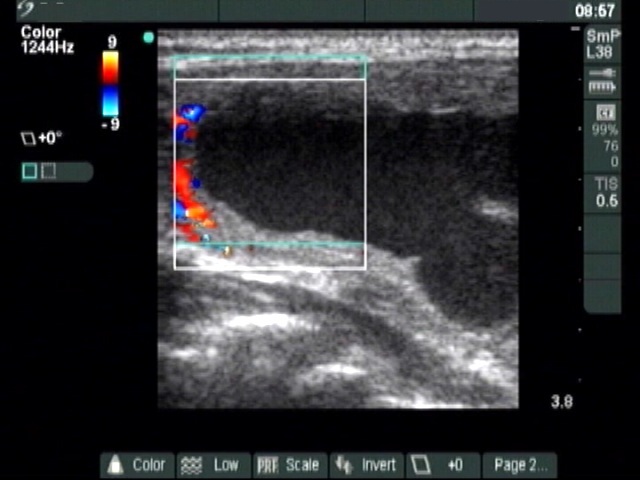

Ultrasonography: The thyroid was echonormal. A large cystic nodule composed of multiple chambers occupied almost the entire right lobe. Several fibrotic bundles dividing the chambers of the cyst were ruptured. The nodule presented halo sign and perinodular blood flow.